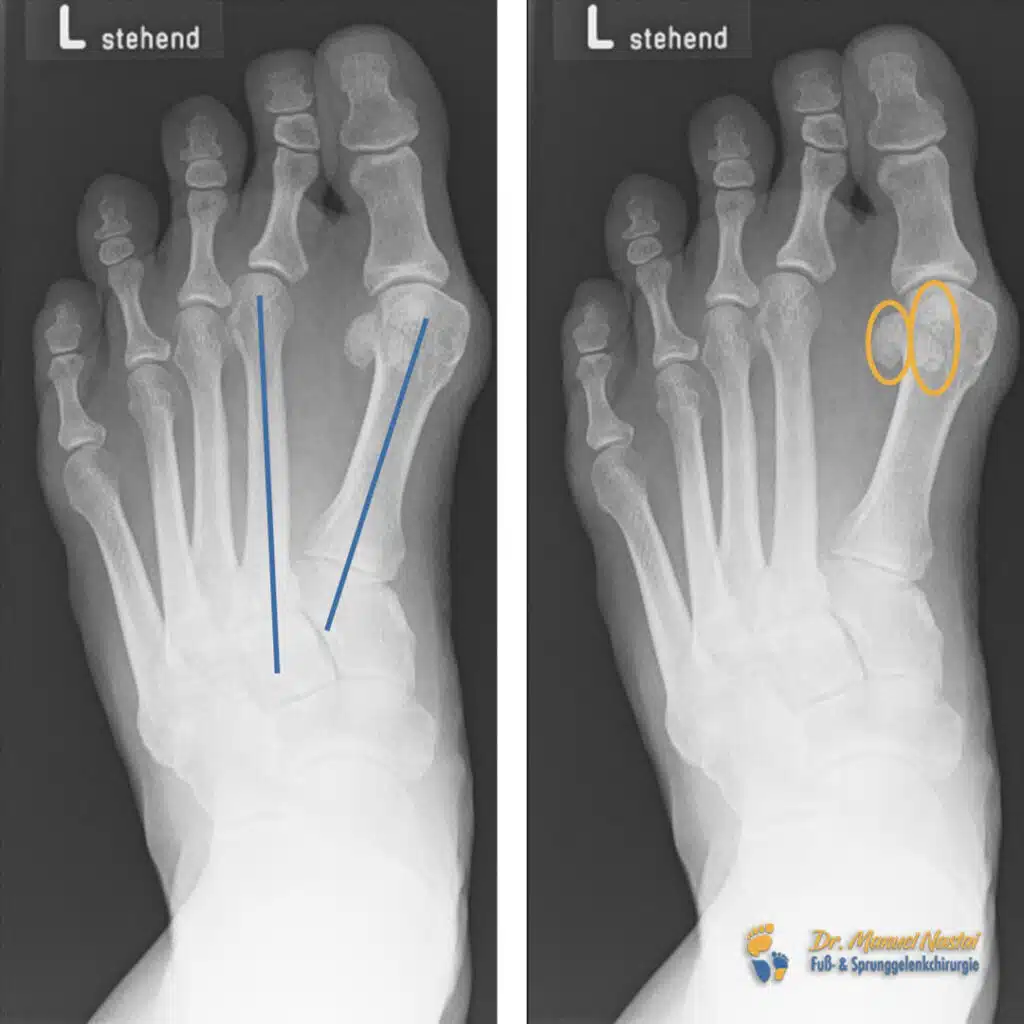

Der Hallux valgus (https://www.drnastai.de/minimalinvasive-hallux-valgus-operation/) ist eine Fehlstellung der Großzehe, bei der diese zunehmend zur Fußaußenseite abweicht. Gleichzeitig wölbt sich das Köpfchen des ersten Mittelfußknochens zur Fußinnenseite hervor (siehe Blaue Linie rechts). Diese Veränderung kann zu Schmerzen, Druckstellen und einer eingeschränkten Gehfähigkeit führen. Ursache sind häufig genetische Veranlagung, schwaches Bindegewebe oder ungeeignetes Schuhwerk. Anfangs kann die Fehlstellung mit Schienen oder Einlagen behandelt werden – bringt dies keine ausreichende Linderung, ist eine operative Korrektur notwendig. Dabei wird die Fehlstellung am Knochen selbst korrigiert. Besonders vorteilhaft sind minimalinvasive Methoden, bei denen über kleinste Schnitte gearbeitet wird, um die Funktion des Fußes wiederherzustellen – ohne große Narben oder lange Ausfallzeit.

Ein fortgeschrittener Hallux valgus betrifft nicht nur die Großzehe, sondern stört die gesamte Statik im Vorfuß. Durch die Abweichung der Großzehe nach lateral erhöht sich der Druck auf die benachbarten Zehen – besonders auf den zweiten Zeh (siehe Orangene Linien auf entlang des zweiten Zehs links). Dieser wird zunehmend in Richtung der Großzehe gedrängt. Typisch ist die Digitus-secundus-supraductus-Fehlstellung: Der zweite Zeh liegt über dem Hallux, ist druckschmerzhaft und führt beim Gehen sowie in geschlossenem Schuhwerk zu deutlichen Beschwerden. Konservative Maßnahmen wie Schienen, Polster oder Zehenspreizer können Symptome zeitweise lindern, verhindern die Progression jedoch häufig nicht. Eine dauerhafte Lösung bietet die chirurgische Korrektur. In unserer Praxis erfolgt sie in der Regel minimalinvasiv: Über einen kleinen Zugang wird der betroffene Knochen neu ausgerichtet und in korrigierter Position stabilisiert.

Die belastete dorsoplantare Röntgenaufnahme zeigt die tatsächliche Stellung des Vorfußes unter Körpergewicht. So werden Achsenabweichungen sichtbar, die in unbelasteter Position oft unterschätzt werden. In deinem präoperativen Bild (siehe „Röntgen präoperativ“) ist der Intermetatarsalwinkel zwischen erstem und zweitem Strahl (IMR1, blau markiert) deutlich geöffnet; zugleich liegen die Sesambeine (orange markiert) exzentrisch seitlich des ersten Mittelfußkopfes. Die farbigen Markierungen (blau/orange) erleichtern Patient:innen das Verständnis für die Deformität und die Ziele der Korrektur.

IMR1 (blau) – was wird gemessen und warum ist das wichtig?

Der IMR1 beschreibt den Winkel zwischen den Längsachsen des ersten und zweiten Mittelfußknochens. Zur Messung werden auf der belasteten Aufnahme die Mittellinien beider Knochen eingezeichnet (jeweils durch den Schaft zur Mitte des Kopfes verlängert); der Winkel zwischen diesen Linien ist der IMR1. Ein vergrößerter IMR1 zeigt einen Metatarsus primus varus an—der erste Strahl steht zu weit nach medial, wodurch sich das Köpfchen des ersten Mittelfußknochens nach innen vorwölbt und die Großzehe nach lateral abweicht. In deinem präoperativen Bild ist dies an der breit geöffneten blauen Winkelmarkierung erkennbar (siehe „Röntgen präoperativ – IMR1 blau“). Ziel der Operation ist es, den IMR1 wieder in den physiologischen Bereich zu reduzieren. Auf dem postoperativen Bild sollte die blaue Winkelmarkierung deutlich kleiner sein (siehe „Röntgen postoperativ – IMR1 reduziert“), was die korrigierte Achsstellung des ersten Strahls belegt.

Sesambeine (orange) – Lage, Bedeutung und Beurteilung

Unter dem Kopf des ersten Mittelfußknochens liegen zwei kleine Knochen—das tibiale (mediale) und das fibulare (laterale) Sesambein. In einer physiologischen Stellung „umfassen“ sie den Mittelfußkopf von plantar, etwa beidseits der zentralen Führungsrinne. Beim Hallux valgus wandern die Sesambeine relativ zum Mittelfußkopf nach lateral. Radiologisch zeigt sich das daran, dass die orange markierten Sesambeine nicht mehr zentriert unter dem Kopf liegen, sondern seitlich „ausweichen“ (siehe „Röntgen präoperativ – Sesambeine orange“).

Diese Lateralisierung ist ein Schweregrad-Indikator und erklärt typische Beschwerden: Die Hebelverhältnisse der Großzehenbeugesehnen verändern sich, die Last verlagert sich ungünstig und es entstehen Druckschmerzen. Nach der Korrektur sollten die Sesambeine wieder mittig unter dem ersten Mittelfußkopf sichtbar sein (siehe „Röntgen postoperativ – zentrierte Sesambeine“). Die Re-Zentrierung ist prognostisch relevant: Sie stabilisiert die korrigierte Achse, verbessert die Lastverteilung im Vorfuß und senkt das Rezidivrisiko.